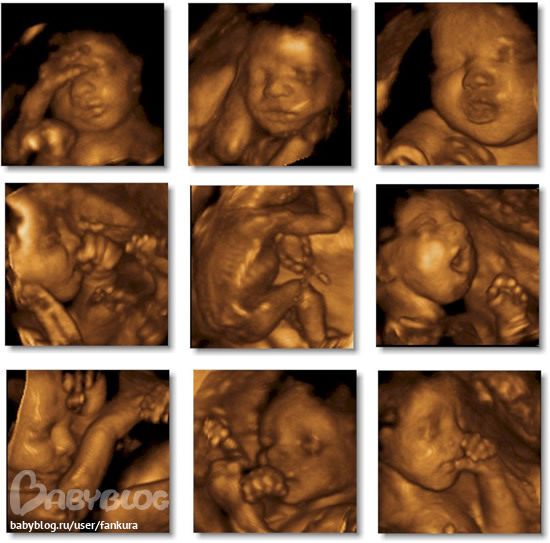

))урааа!!!!узиииии!и срок родов поменялся с аким поворотом посчитав-она мне говорит не беспокойтесь-теперь срок будет неделю отнимаем так ка вы на наделю по развитию узи 1 больше то не 26,04,2012 а 19,04,2012!!!))))

Анют а это вы в 3Д УЗИ? Мне интересно так все хорошо видно))) Мы на следующей недели пойдем))))

да сходите)все советуют)это же новое что то)))))классс